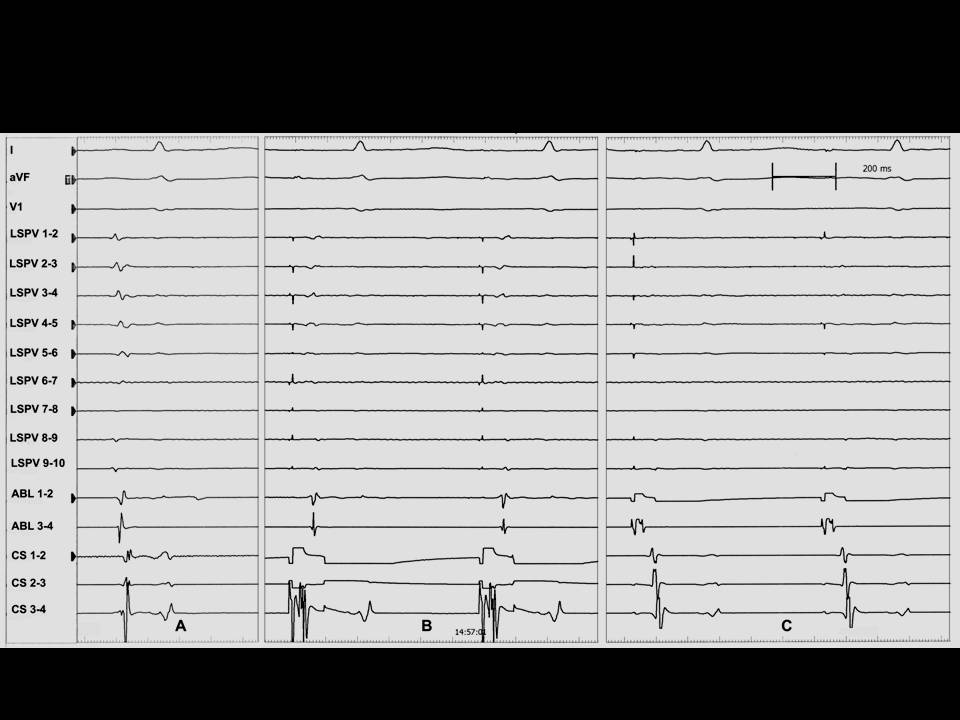

肺静脉隔离术难点